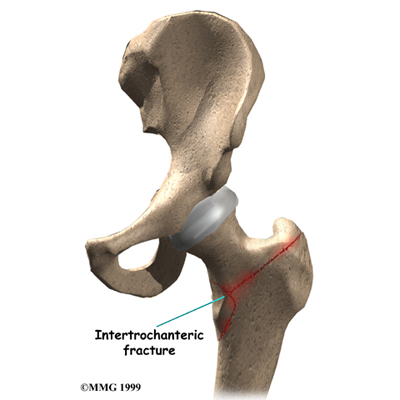

The intertrochanteric region of the hip is just below the femoral neck. A fracture in this area is called an . This type of fracture is most common when a person falls and fractures the hip. There is usually more than one fracture with more pieces of broken bone to be held together.